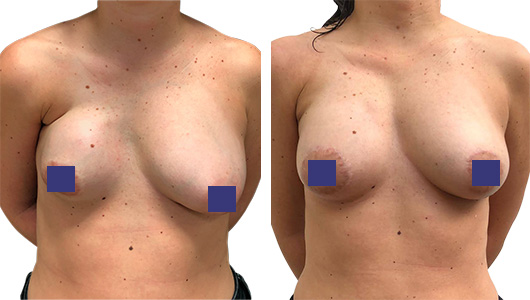

Das unmittelbare Ergebnis ist für den Patienten sehr zufriedenstellend (Abb.3). Die Thorax- und Brustsymmetrie ist stark verbessert.